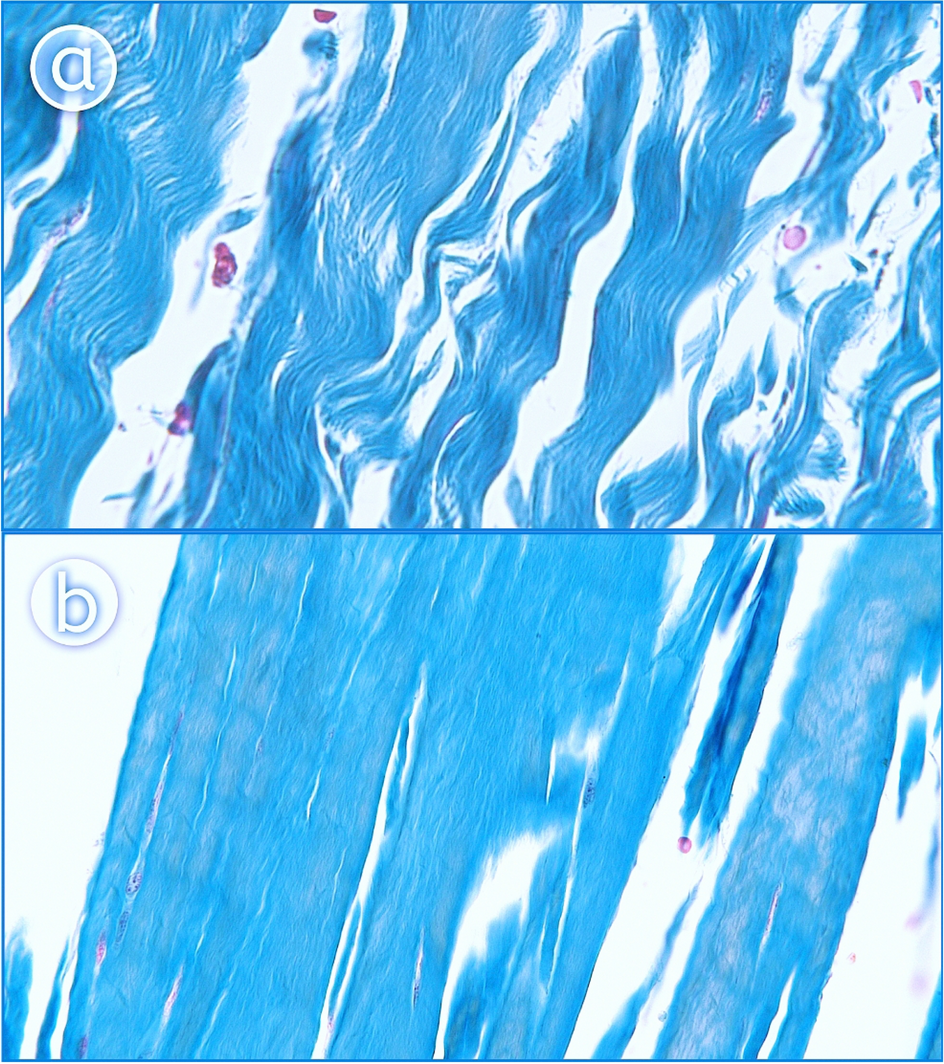

Figure 5

Histological examination of the accessory bands of the popliteus muscle. A 400 magnification—ligament. B 400 × magnification—tendon. The Fig. 5 was taken with Olympus EP50 camera (Olympus Corporation Japan), and the signatures were made in Corel DRAW 12 (https://www.coreldraw.com/pl/pages/coreldraw-12/).